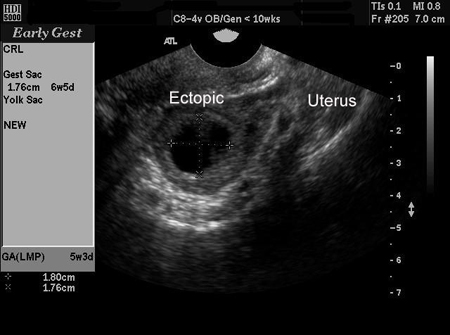

El embarazo ectópico se puede diagnosticar de forma definitiva mediante ultrasonido cuando se observa en los anexos un saco gestacional con saco vitelino o embrión, o ambos.[46] No todos los embarazos ectópicos se pueden visualizar mediante ultrasonido. No obstante, los estudios han demostrado que, con ultrasonido de cada vez mayor resolución y sonografía experta, la ETV es altamente sensible y específica para el diagnóstico del embarazo ectópico. A pesar de eso, sigue habiendo una proporción significativa de casos (de entre el 5% y el 42%) en el que el embarazo, ya sea intrauterino o ectópico, no se puede visualizar mediante ultrasonido. En estos casos, se usa el término descriptivo de embarazo de ubicación desconocida.[47][48][Figure caption and citation for the preceding image starts]: Imagen de ultrasonido de embarazo ectópicoDe la colección de la Dra. Melissa Fries; usado con permiso [Citation ends].

[Figure caption and citation for the preceding image starts]: Imagen de ultrasonido de embarazo ectópicoDe la colección de la Dra. Melissa Fries; usado con permiso [Citation ends].